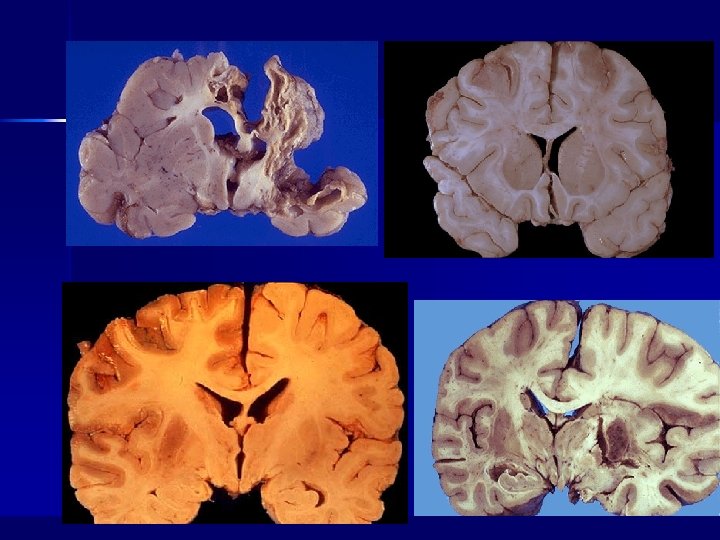

Stroke n n n Second important cause of death Physical and pshychosocial handicap Lesions of brain parenchima due to pathology of cerebral circulatory system that leads to hemorrhageae or ichemic lesions

Cerebral infarctus n Flow decrease increase of oxygen extraction Celular death dramatic decrease of oxygen extraction, vasoplegia (due to acidosys, release of other substances) increase of flow n Penumbra: n – Critical flow, enough for some of the processes required for cell survival – Not enough for cell function – Recovery if blood flow increases